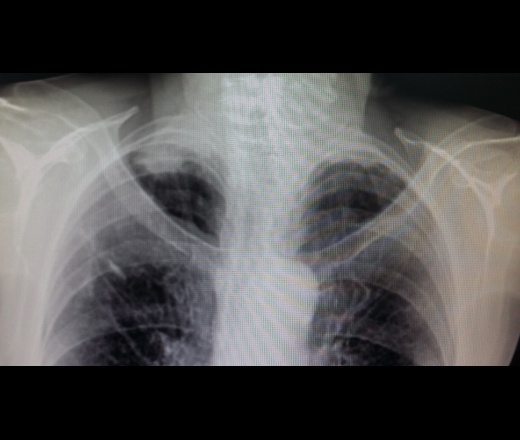

Рентгеновские снимки опухоли Панкоста